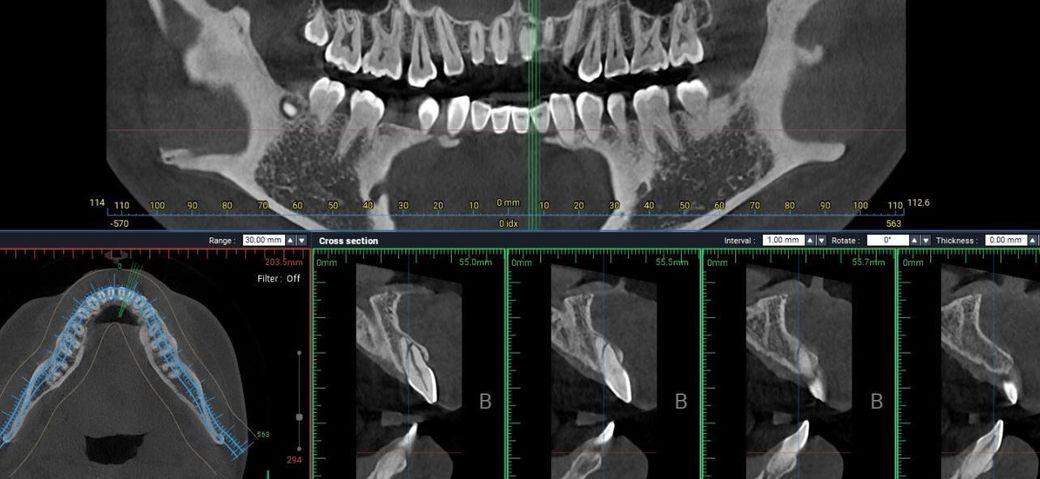

이빨 CT사진인데 뿌리쪽 크랙일까요

최근에 넘어져서 이빨을 다쳤었는데

현재 육안상은 밑에가 금이가있습니다

치과를 다녀왔는데 뿌리쪽에 크랙일까요….

확인부탁드립니다 -> 네 뿌리 부위 사선으로 크랙의 상황 같습니다.

CT사진상으로 봤을 경우 치근에 큰 금이 가있는것으로 보입니다.

저정도의 금이라면 치아에 극심한 통증이 있게 됩니다 통증이 없는것이라면 영상상에만 검은 줄이 보이는것일수도 있습니다.

자세한 확인을 위해서 치과에서 진료를 받아보는 것을 권유드립니다.